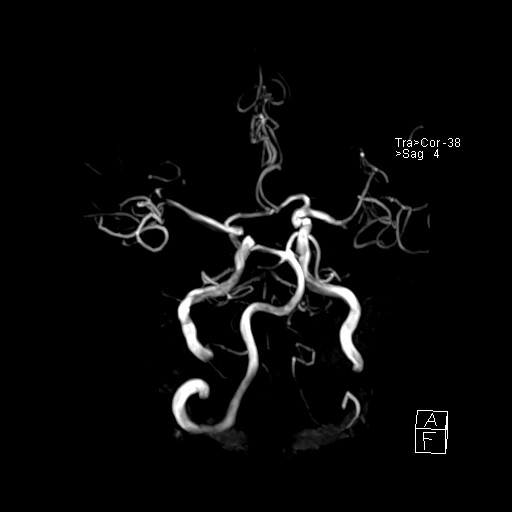

239716 - VILLANUEVA, WILLIAM A. - Number 4 |

239716 - VILLANUEVA, WILLIAM A. - Number 4 |